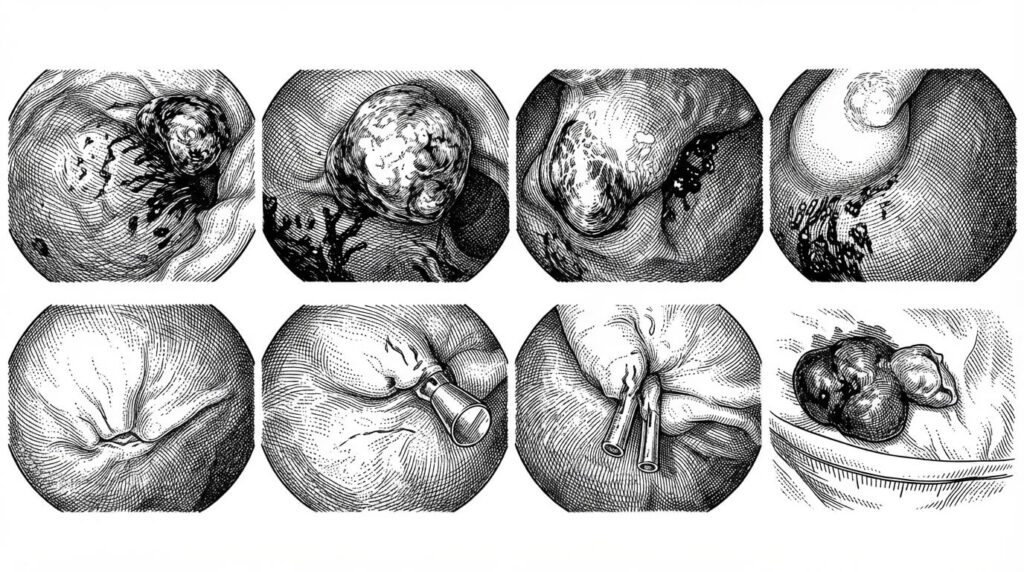

An elderly patient presented with massive hematemesis and drop in hemoglobin from 13 to 9 gr/dl. After hemodynamic stabilization an EGD was performed. A large antral polypoid lesion with stigmata of hemorrhage was seen (A, B).

The polyp had a large and thick pedicle (C). The pedicle was injected with saline-epinephrine mix (1:10,000) (D). Endoscopic resection was performed using a snare (E). The resection defect was closed using two clips (F, G).  Panel H shows a 4 cm large pedunculated polyp. Histology showed a gastric hyperplastic polyp with no malignant features. The patient did not have any additional bleeding episodes.